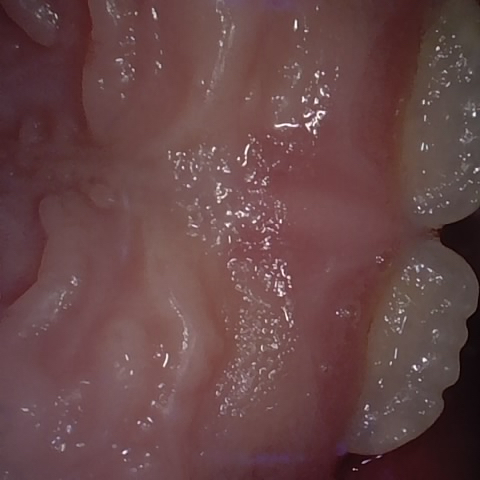

Annotated as "Good"